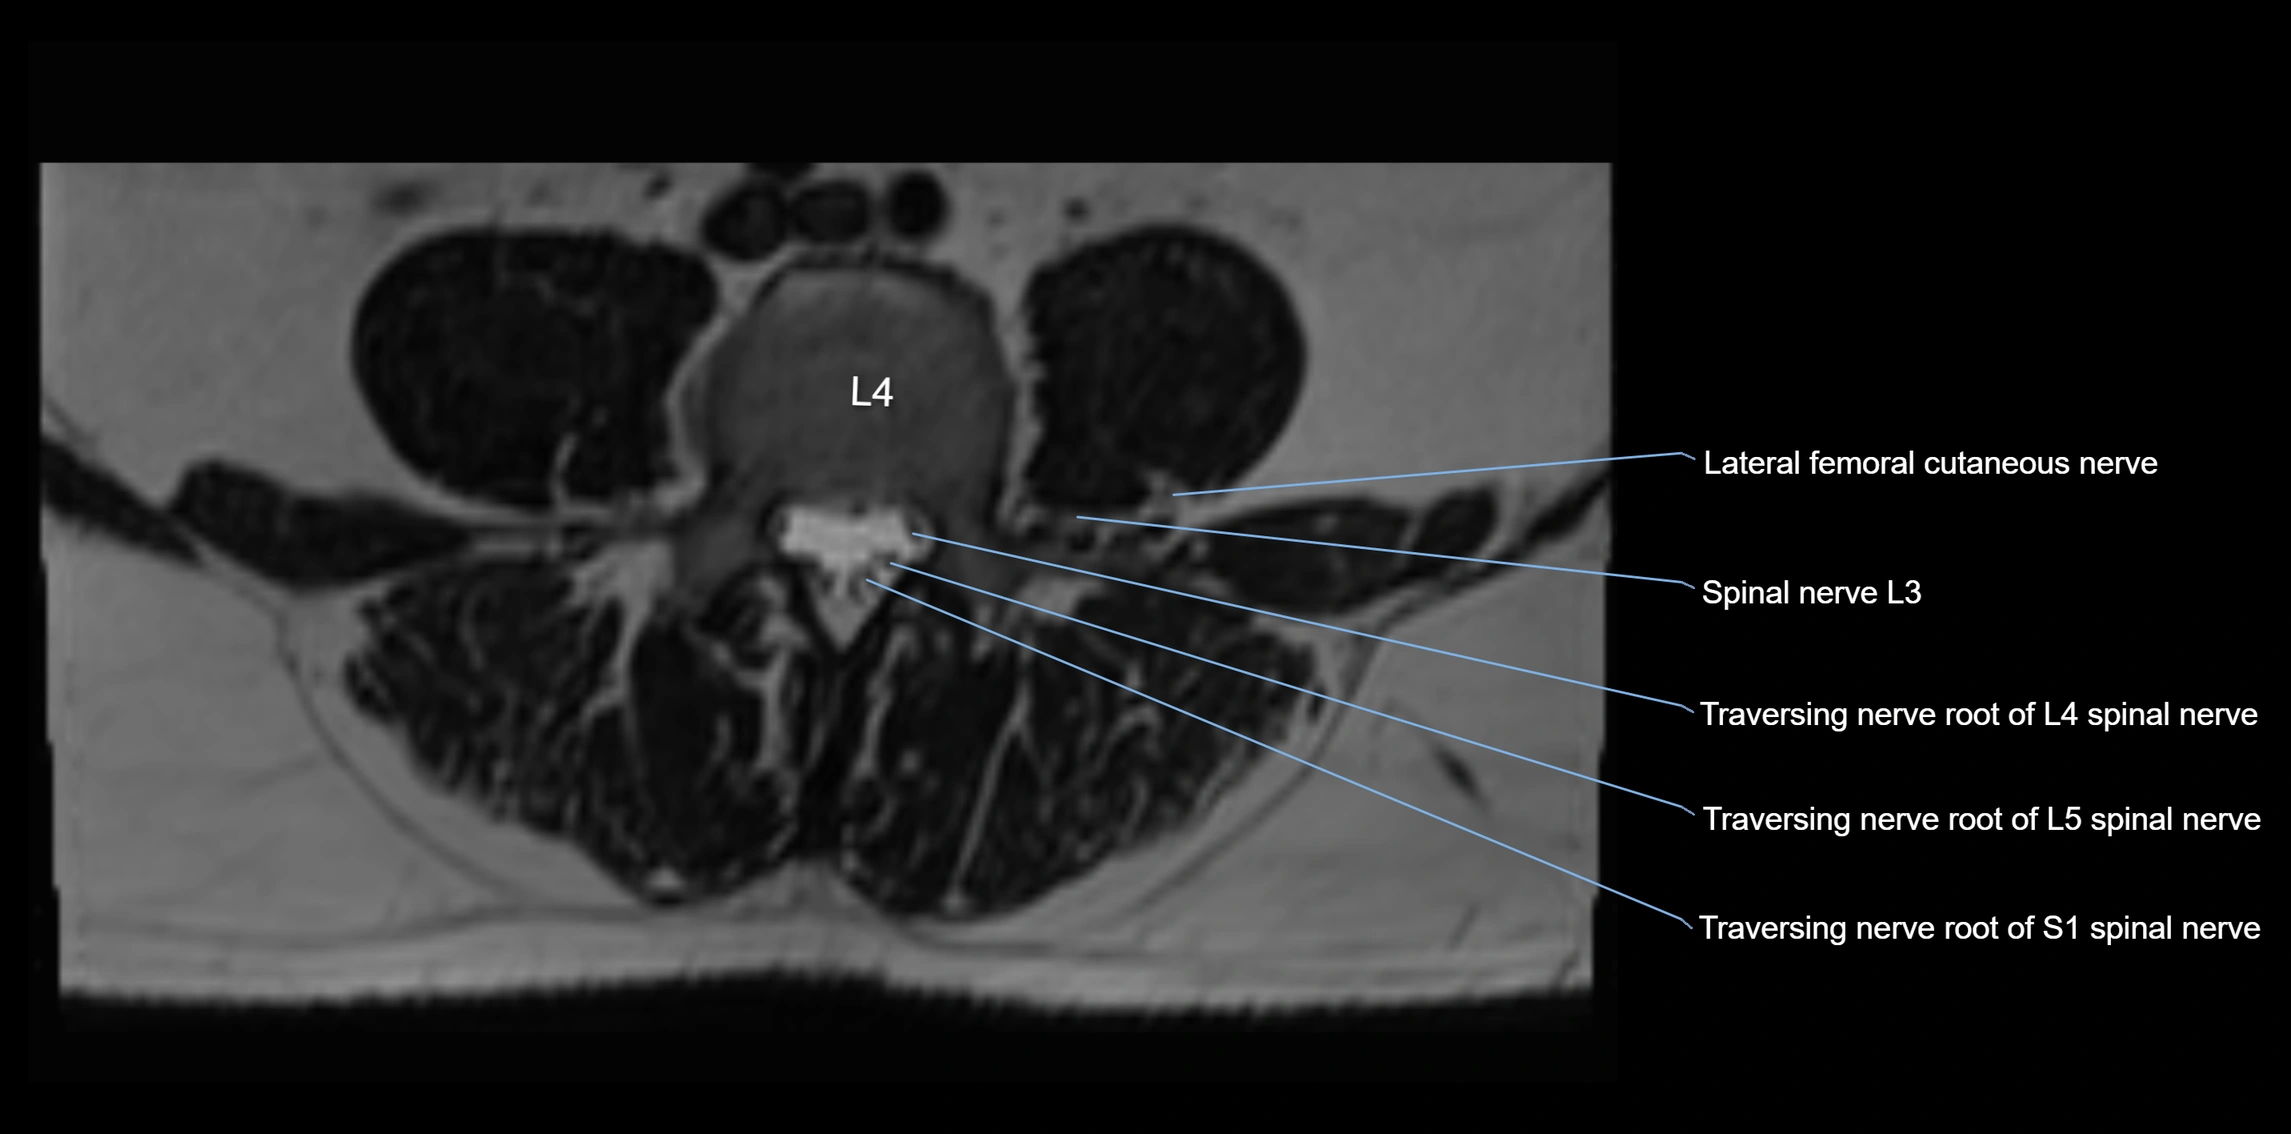

MRI Appearance

T1-weighted images:

• Nerve appears as a very thin low-to-intermediate signal intensity structure

• Surrounded by bright fat, aiding visualization

T2-weighted images:

• Nerve shows intermediate to mildly hyperintense signal compared to muscle

• Pathological involvement appears brighter

STIR (Short Tau Inversion Recovery):

• Normal nerve appears dark

• Inflamed or entrapped nerve appears bright hyperintense

T1 Fat-Sat Post-Contrast:

• Normal nerve enhances minimally

• Pathologic nerve (neuritis, entrapment, tumor infiltration) shows focal or diffuse enhancement

3D T2 SPACE / CISS:

• Nerve appears intermediate to mildly hyperintense compared to muscle

• Surrounded by bright fat or CSF, improving visualization

• Best sequence for mapping small pelvic nerves such as the anococcygeal